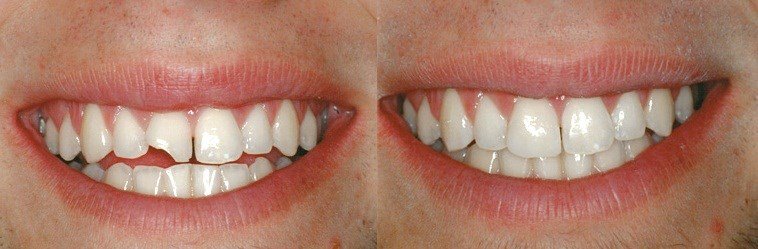

«ПЛОМБА» і «РЕСТАВРАЦІЯ» – у чому різниця?

Ви бачите пломби на своїх зубах? – значить це справжні «пломби». Реставрацію не видно! «Пломба» – це лише закриття дефекту (порожнини) зуба. Вона рівна і гладка – і в цьому якраз основна проблема. Пломба не відновлює контакт з протилежними та сусідніми зубами, що з часом буде призводити до їх зміщення та порушення жування. Такі проблеми…